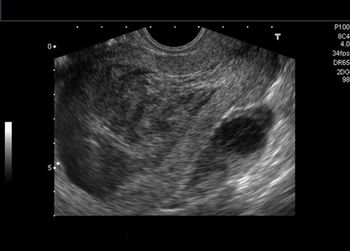

What is your diagnosis in this middle-aged woman with abnormal vaginal bleeding?